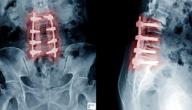

• الجراحة، قد تكون الجراحة خيارًا إذا لم تنجح العلاجات الوقائية، إذ يعتمد النوع المناسب من الجراحة على سبب الانضغاط؛ إذ يمكن للجراحين دمج الفقرات معًا أو إزالة توترات العظام أو زيادة المسافة بين الفقرات.

سيحاول الطبيب العثور على السبب المؤدي إلى ضغط النخاع الشوكي، ويتضمن ذلك عادةً اختبارات جسدية وعصبية تتضمن أسئلة واختبارات لفحص وظائف المخ والحبل الشوكي والعصب، كما سيتحقق الطبيب أيضًا من وظيفة العضلات وردود الفعل، وعادةً ما تُشخص الحالة عن طريق اختبارات التصوير الآتية:[١]

• الاشعة المقطعية.